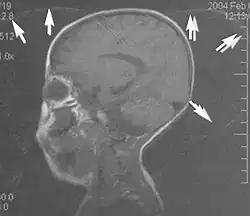

Motion artifacts

A motion artifact is one of the most common artifacts in MR imaging.[2] Motion can cause either ghost images or diffuse image noise in the phase-encoding direction. The reason for mainly affecting data sampling in the phase-encoding direction is the significant difference in the time of acquisition in the frequency- and phase-encoding directions.[1] Frequency-encoding sampling in all the rows of the matrix (128, 256 or 512) takes place during a single echo (milliseconds). Phase-encoded sampling takes several seconds, or even minutes, owing to the collection of all the k-space lines to enable Fourier analysis. Major physiological movements are of millisecond to seconds duration and thus too slow to affect frequency-encoded sampling, but they have a pronounced effect in the phase-encoding direction. Periodic movements such as cardiac movement and blood vessel or CSF pulsation cause ghost images, while non-periodic movement causes diffuse image noise (Fig. 1). Ghost image intensity increases with amplitude of movement and the signal intensity from the moving tissue. Several methods can be used to reduce motion artifacts, including patient immobilisation, cardiac and respiratory gating, signal suppression of the tissue causing the artifact, choosing the shorter dimension of the matrix as the phase-encoding direction, view-ordering or phase-reordering methods and swapping phase and frequency-encoding directions to move the artifact out of the field of interest.[1]